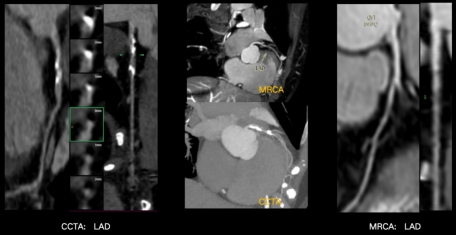

但是到目前為止,冠脈的磁共振成像,一直是臨床上的一個技術挑戰。因為冠脈走形迂曲,結構細小,受心臟搏動及呼吸影響較大,容易掃描失敗率高、掃描時間長、圖像不佳,因此在臨床很難常規開展。但是基于飛利浦的無液氦2.0雙芯磁共振,通過極致均勻的無液氦磁體以及魔方平臺的強強硬件組合,大幅改善了冠脈掃描的成功率,極大地提升了掃描速度,并且保證了較好的圖像質量。目前無液氦2.0雙芯磁共振,可以在無需注射對比劑的前提下,無創、無輻射的帶來媲美金標準CTA的檢查效果。甚至CTA在遇到鈣化斑塊時,偽影影響可能過高評估狹窄程度,從而導致狹窄評估可能偏差,但雙芯磁共振的冠脈檢查能夠清晰顯示冠脈管腔結構,無偽影影響,狹窄評估更準確。